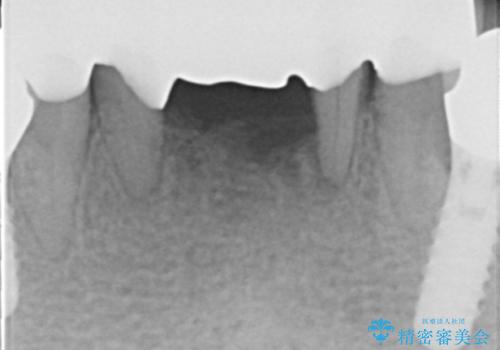

抜歯後歯肉の治癒を十分に待ったのち、ブリッジによる補綴治療を行いました。

歯周病が重度であったため抜歯後の歯肉の陥凹が大きく、GBRや歯肉移植による歯周組織の再建をおすすめしましたが、ご希望されませんでした。

上の前歯の再根管治療もおすすめしましたが、必要性を感じないとのことで土台のやりかえだけをご希望されました。